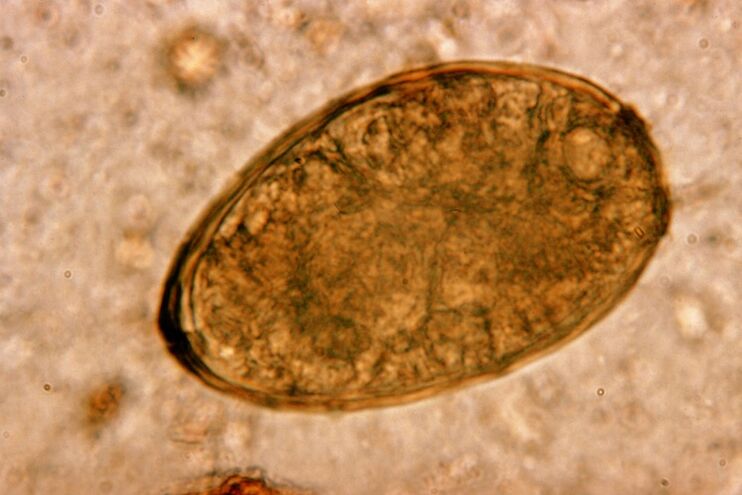

The most dangerous for the respiratory system are flatworms, especially flukes and toxocaras.After attaching to the lungs, they cause paragonimiasis and toxocariasis - serious diseases accompanied by the destruction of lung tissue and a progressive inflammatory process.

Flatworm penetration into the child's lungs causes him to cough.If left untreated, the inflammatory process progresses and enters a stage accompanied by mucus formation.Coughing sputum may contain blood.This alarming manifestation should force parents to immediately consult an infectious disease doctor.

They happen to live in the lungs in pairs, forming cysts in the bronchi.Infestation occurs when eating crabs and crayfish infected with the parasite.Once in the gastrointestinal tract, pulmonary embolism penetrates the peritoneum and reaches the lungs through the diaphragm, causing persistent coughing in the patient.

It happens that small pulmonary helminths, which belong to the class of trematodes, "specialize" in specific parasites in the lungs.It causes more serious problems in the respiratory system than roundworms, for example.

At the site of its localization, an infiltrate appears and bleeding develops, as a result of which the cavity appears full of worm metabolites, dead parasites and lung tissue.The harm from pulmonary embolism is exacerbated by the fact that it is a long-lived liver and can live in the host's body for up to 20 years.